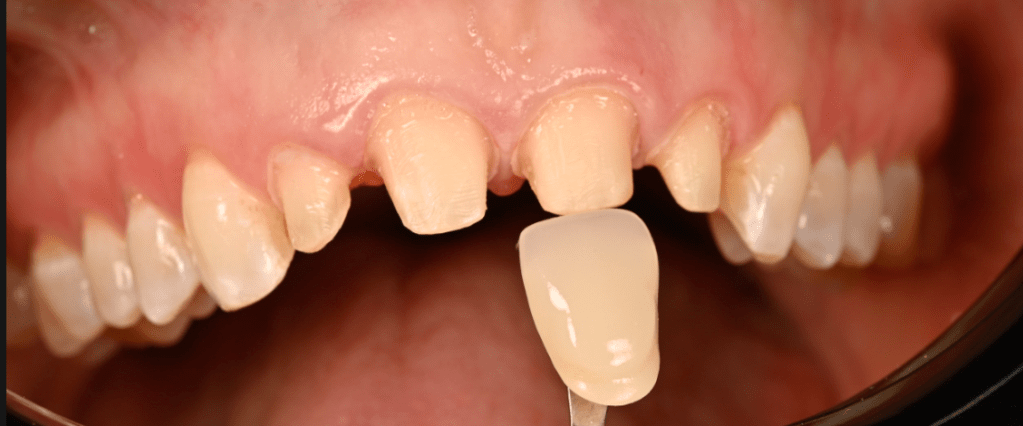

Preparations with shade tab A1, patient requested no characterization in final crowns